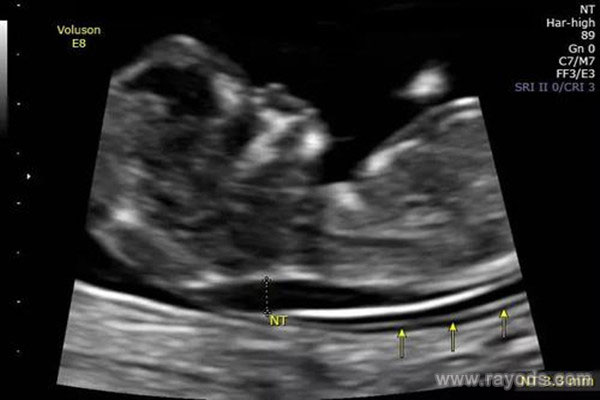

nt值1.9mm是男是女 已生宝妈透露怀男孩女孩nt值

在得知自己怀孕后,不少人都沉浸在幸福的喜悦之中,而喜悦过后,大家则对宝宝的性别感到好奇,怀的是男是女呢?长得像妈妈多一些还是像爸爸多一些?等等,很多人在好奇心的..

nt怎么看男宝还是女宝 已生宝妈告诉你答案

nt怎么看男宝还是女宝 nt检查,怀孕早期必检的孕检项目,相信很多孕妈妈都是知道它的。nt检查与其他的检查项目不同,它是用B超检查胎儿颈部位置,通过胎儿颈部透明层的厚度..